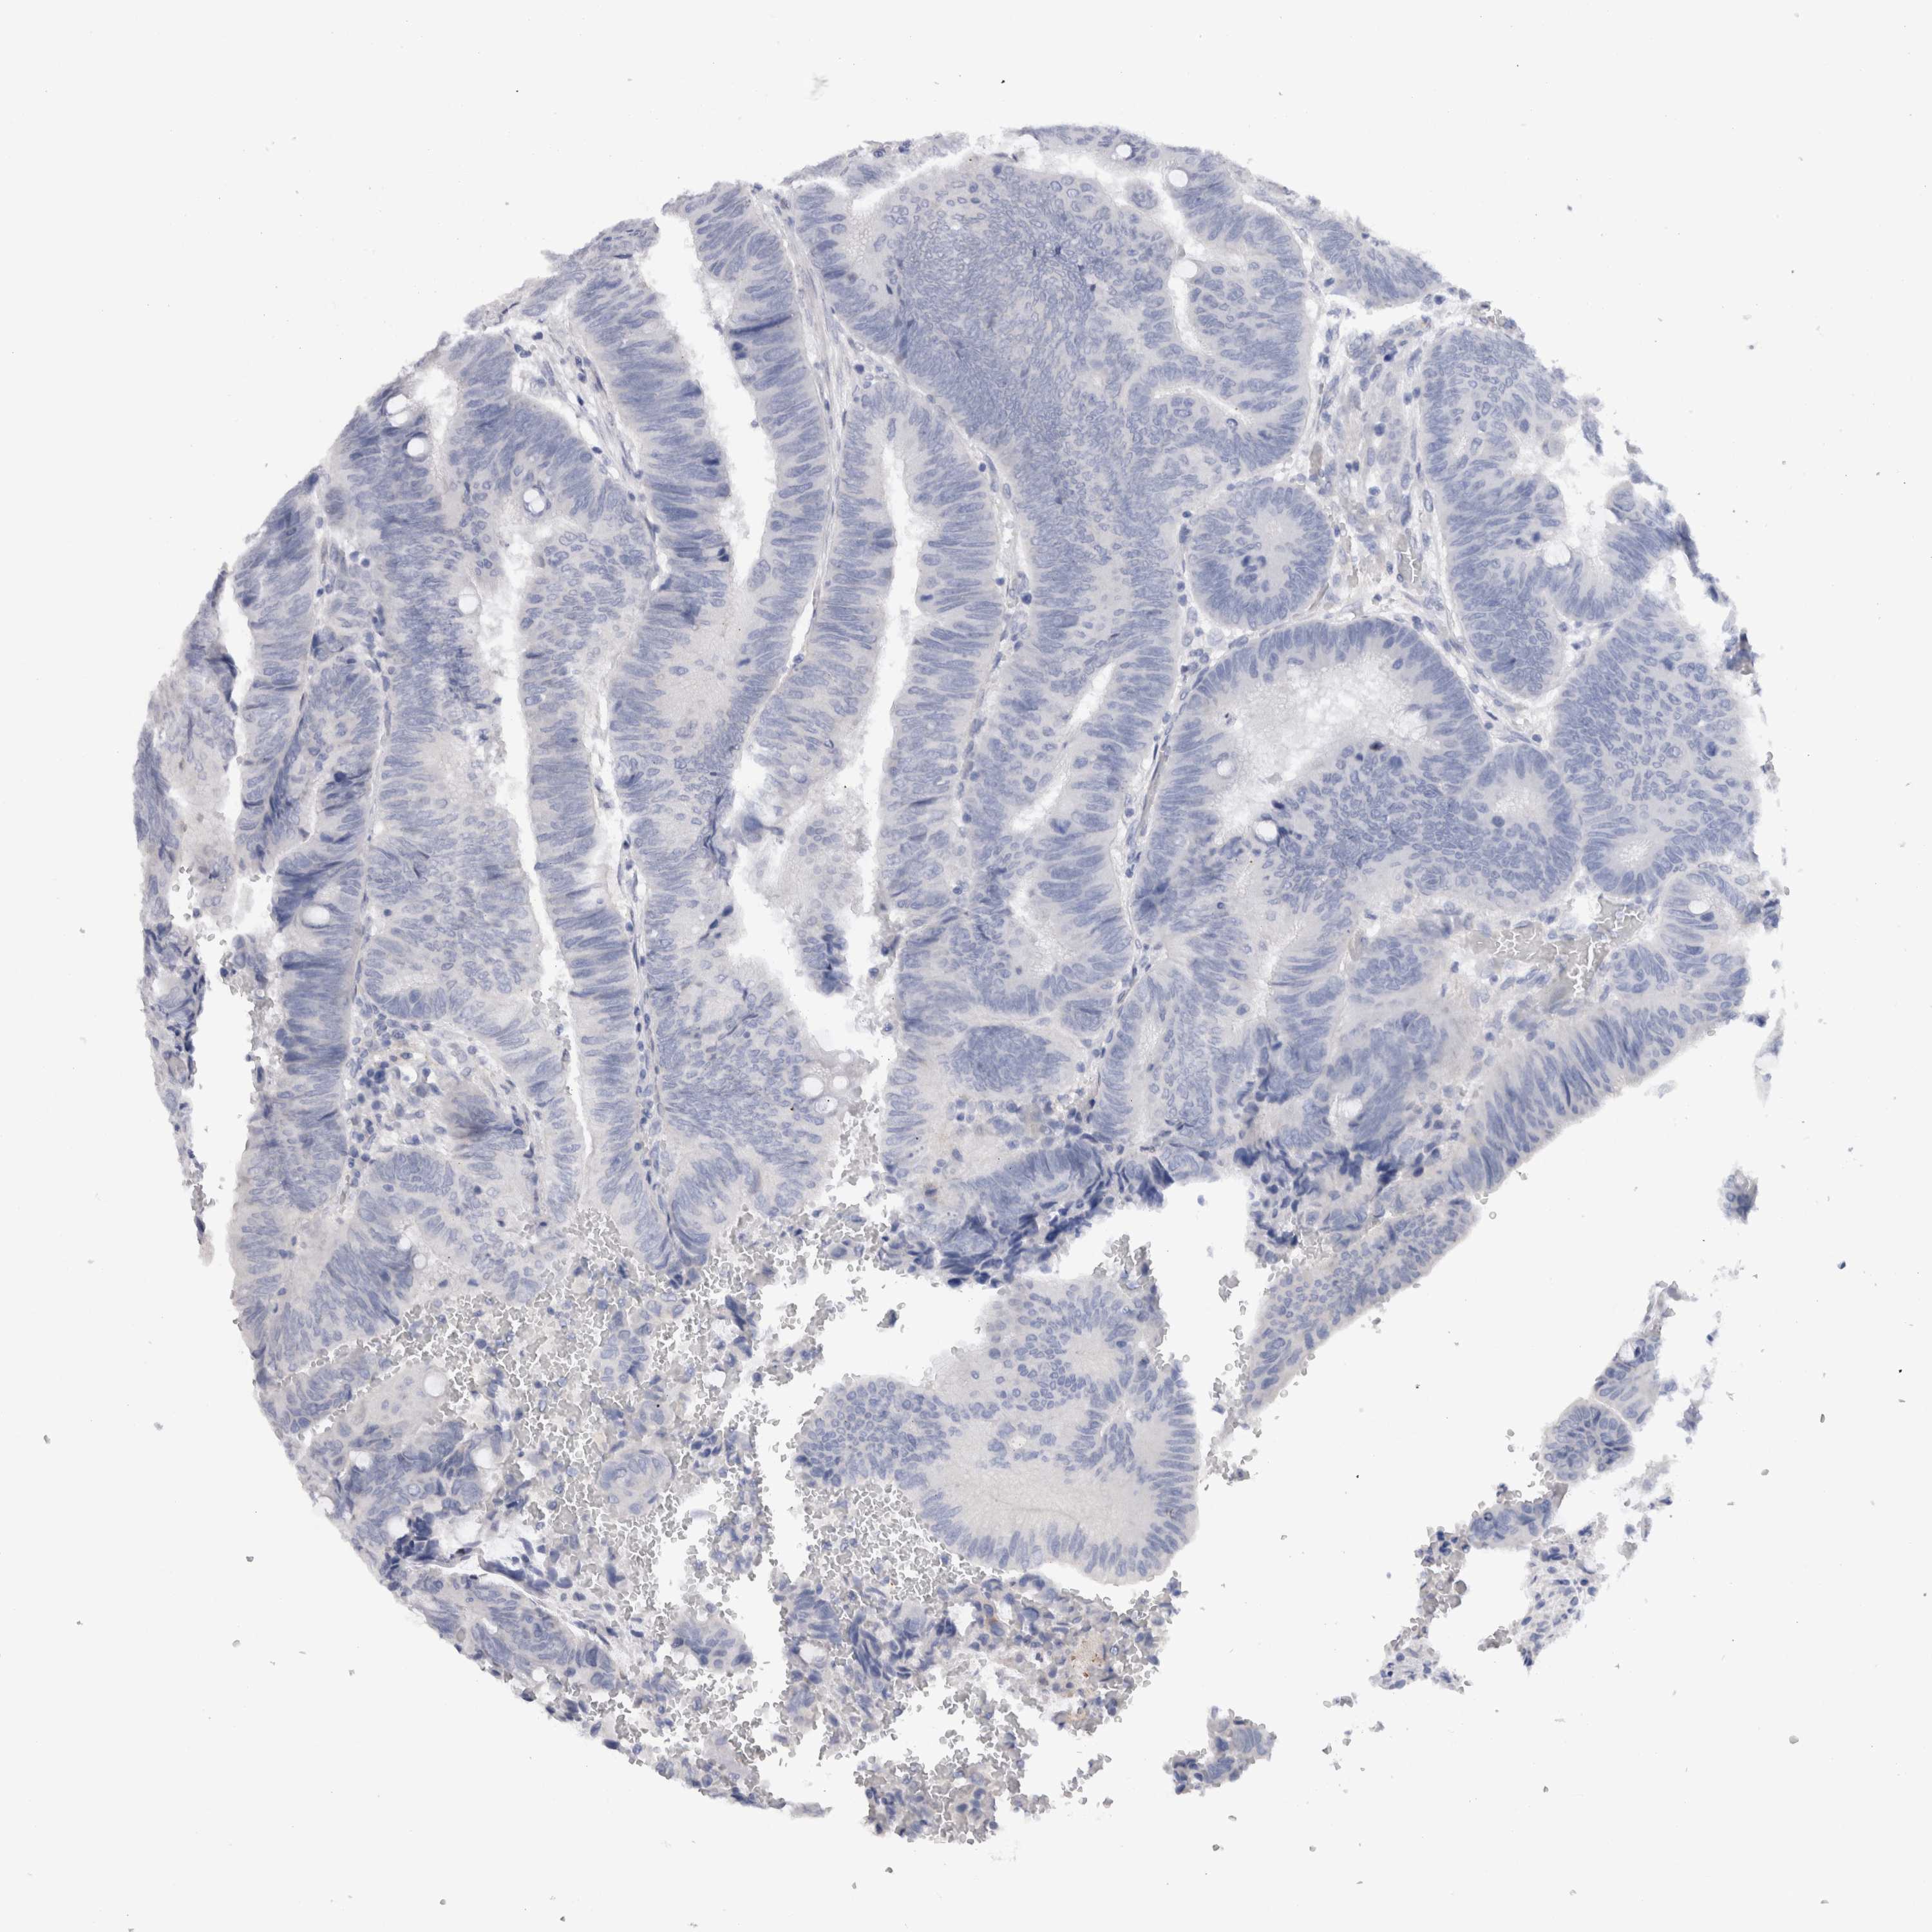

Colorectal cancer

Colon adenocarcinoma